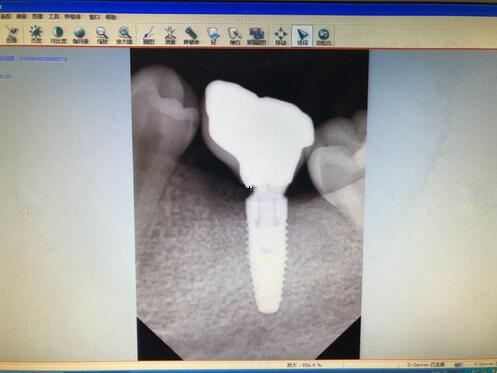

廣州牙齒整形種植牙果圖

在手術(shù)的過(guò)程中打了麻藥,而且醫(yī)生也一直在詢問有沒有什么不舒服的感覺,如果有不舒服,一定要第一時(shí)間告訴他,所以說(shuō)還是比較舒適的整個(gè)過(guò)程。我的牙齒一共壞了四顆,所以說(shuō)手術(shù)的時(shí)間還是比較久的,大概是用了將近三個(gè)小時(shí)的時(shí)間才完全結(jié)束,在這三個(gè)小時(shí)里面,口腔一直長(zhǎng)著,還是覺得有一些口干的。

現(xiàn)在牙齒已經(jīng)恢復(fù)的相當(dāng)?shù)暮昧?,大家可以看到這幾顆種植牙,看起來(lái)比之前的牙齒都更加好看了呢,而且更加的潔白也結(jié)實(shí)了不少,之前不敢吃的一些食物,現(xiàn)在都可以吃了。